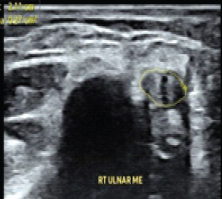

Ultrasound and Fluoroscopy-Guided Percutaneous Hydrotenotomy with Open Conversion for Symptomatic Periligamentous Calcification of the Medial Collateral Ligament: A Case Report

Brigitte Lieu , Suhas Rao Velichala , Andrew Cuthbert , Maya Johnson , Jonathan Brett Goodloe ………………………………p.194-198